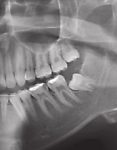

Retinierter Zähne

Wir bieten routinierte Entfernung retinierter Zähne. Bei besonders schwieriger anatomischer Lage (direkte Lage am n.alveolaris inferior) bieten wir durch Einsatz piezochirurgischer Osteotome die derzeit weichgewebs-schonendste Methode der Entfernung insbesondere der unteren Weisheits-zähne an.

Der Einsatz eines Chirurgielasers und eine direkte postoperative photodynamische Softlaserbehandlung minimieren die postoperativen Beschwerden unserer Patienten.

Auch die Freilegung retinierter Zähne zur anschließenden

kieferorthopädischen Eingliederung in die Zahnreihe wird im Bedarfsfall durch den Einsatz piezochirurgischer Präparationsmethoden durchgeführt.